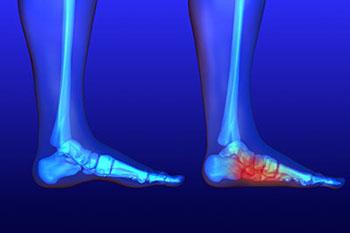

Millions of people are affected with diabetes each year. Diabetes damages blood vessels in all parts of the body, especially the feet. The legs and feet may develop slow blood flow, which causes neuropathy (nerve damage). Once a diabetic patient develops neuropathy,...